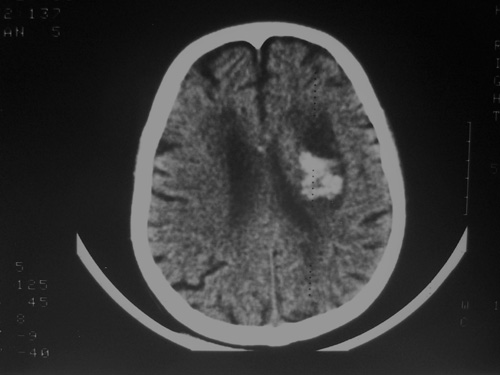

患者63岁,男。左侧肢体活动不灵一小时来诊。bp:175/75;家人否定有脑出血、脑梗死及其他病史。有嗜酒习惯。ct:右侧外囊区见不规则高密度影,边清,肯定是出血。可其周围低密度,边清,ct值与脑脊液相近,不像是水肿影,好似一软化灶形成。这种混合型病灶少见,请老师给予指导一下。

高密度灶为新鲜出血,临近低密度区为软化灶,可能为陈旧性梗塞或出血致。

软化灶出血,左侧脑室轻度受压。

首先考虑脑软化灶并出血。

囊性胶质瘤破裂出血不完全排除.

软化灶内脑出血,且该软化灶应是既往出血所致.这样的病例也不少见.

双侧额岛叶萎缩,病者有嗜酒习惯,考虑可能由酒精中毒引起的脑软化灶,合并脑出血,右基底节区亦有软化灶